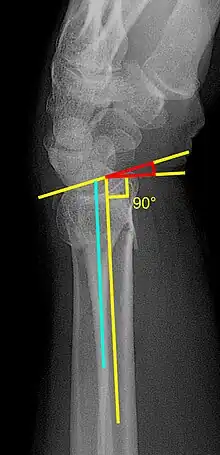

A dorsal tilt of a distal radius fracture is shown in red in image at right. The angulation goes between:[1]

- A line drawn between the distal ends of the articular surface of the radius on a lateral X-ray.

- A line that is perpendicular to the diaphysis of the radius.

Sometimes, the diaphysis of the radius is hard to distinguish from the ulna, and a line between them (turquoise line in image) may be used instead.[2]

The angle normally has volar tilt of 11° to 12°. The most common fracture pattern usually demonstrates malalignment of this angle and collapse in a dorsal direction. A dorsal tilt of 0° (11° - 12° deviation from normal anatomic position) causes a substantial risk of developing pain and impaired function.[3] After closed reduction, a residual dorsal tilt of a maximum of 5° (16° - 17° deviation) is regarded as the maximal residual angle for a satisfactory result.[3]

The radial inclination of a distal radius fracture is shown in red in image at right. The angle is measured between:[4][5]

- A line drawn between the distal ends of the articular surface of the radius on an AP view of the wrist.

- A line that is perpendicular to the diaphysis of the radius.

Radial inclination is normally 21-25°.[6]